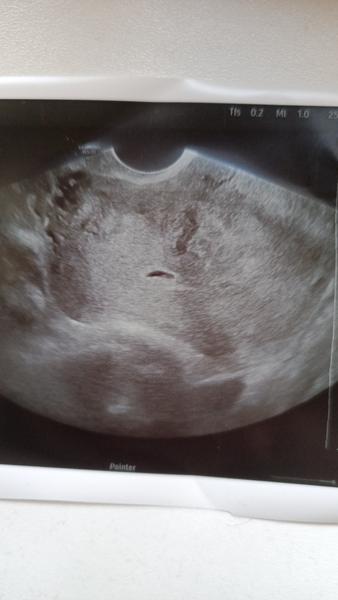

@renatajaja je tam 🙂 jeste je brzy videt neco vic! Ale vsechno je na dobry ceste ❤️

Ja byla dnes na ultrazvuku. Byl videt zloutkovy vacek a zaklady embrya. Dalsi UTZ za 14 dni. ❤️

Jo a to me chtel objednat az za 3-4 tydny, ja si vydupala 14 dnu… a me foto z ultrazvuku vypada dost podobne tomu tvemu 😂

@lenie82 kolikátý ? patnáctý den po ET. V pondělí jdu znova na ultrazvuk. Tak držím pěstičky ❤️🙏 čekat zda začne být srdíčko je strašný 🙈🙈🙂

Tak se v pondeli tesim na dalsi fotku… ❤️